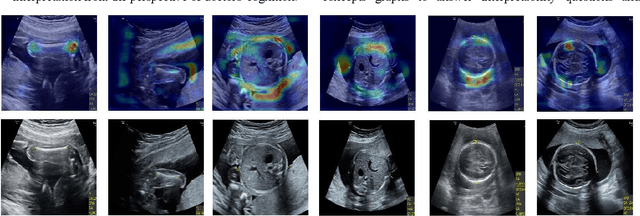

Abstract:Although deep neural networks (DNN) have achieved state-of-the-art performance in various fields, some unexpected errors are often found in the neural network, which is very dangerous for some tasks requiring high reliability and high security.The non-transparency and unexplainably of CNN still limit its application in many fields, such as medical care and finance. Despite current studies that have been committed to visualizing the decision process of DNN, most of these methods focus on the low level and do not take into account the prior knowledge of medicine.In this work, we propose an interpretable framework based on key medical concepts, enabling CNN to explain from the perspective of doctors' cognition.We propose an interpretable automatic recognition framework for the ultrasonic standard plane, which uses a concept-based graph convolutional neural network to construct the relationships between key medical concepts, to obtain an interpretation consistent with a doctor's cognition.

Abstract:The implementation of medical AI has always been a problem. The effect of traditional perceptual AI algorithm in medical image processing needs to be improved. Here we propose a method of knowledge AI, which is a combination of perceptual AI and clinical knowledge and experience. Based on this method, the geometric information mining of medical images can represent the experience and information and evaluate the quality of medical images.